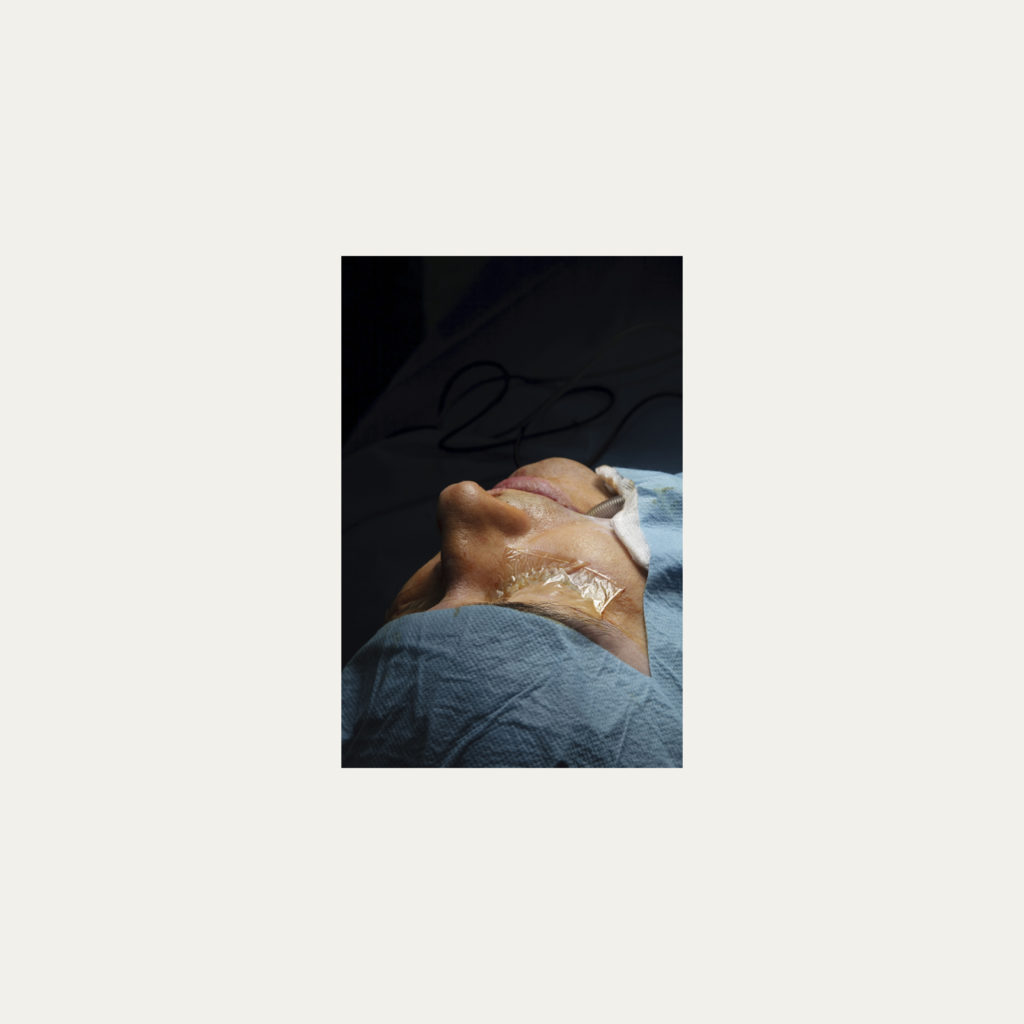

« Nature Morte » est la recherche de l’instant, pendant une intervention chirurgicale où la tête du patient opéré se retrouve seule dans le champ photographié. Aucune main intervenant, peu d’instruments chirurgicaux visibles, laissent le fragment de corps opéré existé pour lui-même. Les têtes, ainsi isolées, en deviennent presque des objets.

Cette approche est intensifiée par la présentation : dans de grands cadres carrés et passe-partout blancs, les photos de petit format font référence aux papillons épinglés de la collection d’un entomologiste.

Face à ces images, une forme de recueillement est nécessaire, s’approcher doucement pour s’approprier tous les détails des images.

Le caractère éminemment esthétique est souligné/donné par les gammes de couleur, la lumière précise sur la tête photographiée, les brillances partielles, renforçant également l’aspect pictural, les textures réelles.

L’humain présent dans ces images est celui qui rompt avec l’invisible et donne à voir l’architecture même de sa chair.